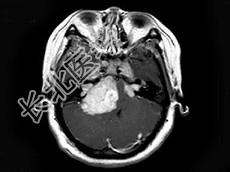

- 单项选择题女,22岁, 胸背部及头皮下多发红色丘疹状突起,伴头痛, 听力下降半年,行头颅MRI平扫及增强扫描如图, 最可能的诊断为 ( )

D、神经纤维瘤病NF-Ⅱ型